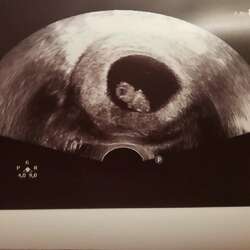

Jaa hooor ook ik kan weer zeggen na 2 miskramen te hebben dat ik weer zwanger ben馃グ

Ik hoop dit keer dat mijn kleine wondertje zicht goed zal nestelen in mijn buik馃ゲ